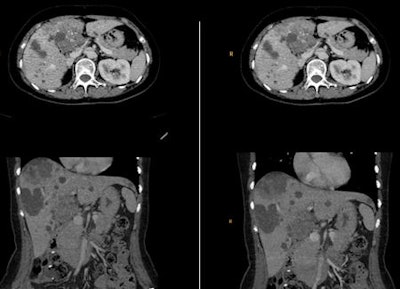

For the clinical evaluation, the researchers performed low-dose CT on cancer patients who had had a previous full-dose examination. The body mass index (BMI) CT protocol was modified so that patients received the next CT scan at one BMI/dose level lower. They obtained a dose reduction of about 50%, while retaining an image quality at least equal to the full-dose examination.

Implementing a hybrid iterative reconstruction technique has enabled radiologists at the Technical University of Munich (TUM) to achieve an average dose reduction of about 50% in CT examinations, but they stress the level of dose reduction depends critically on the initial settings, type of examination, and subjective image criteria -- and image quality requires constant evaluation.

Sophisticated image reconstruction algorithms have been developed over the past few years. A key factor has been the significant increase in computing power necessary for image reconstruction algorithms beyond standard filtered back projection (FBP). At the TUM, radiologists have worked on the clinical integration of iDose from Philips Healthcare on a 256-slice multidetector CT unit (Brilliance iCT) to lower radiation dose while retaining an image quality at least equal to standard FBP reconstruction. They presented their findings at the recent RSNA congress.